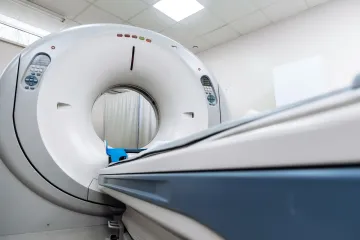

Tuberkuloza je potencijalno ozbiljno stanje, ali se može izliječiti ako se liječi odgovarajućim antibioticima. Treba pripaziti na ovih šest simptoma: